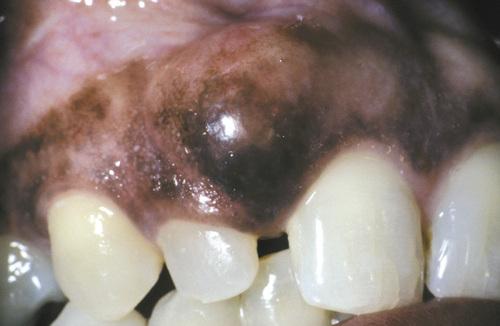

Clinical Features

- soft tissue counterpart of lateral periodontal cyst

- predilection for mandibular canine/premolar area

- found in patients in the fifth and sixth decades

- almost invariably on facial gingiva or alveolar mucosa

- painless, domelike swellings less than 0.5 cm

- often bluish or blue-gray

gingival cyst of the adult

Tense, fluid-filled swelling on the facial gingiva. Surgical excision revealed superficial “cupping out” of the alveolar bone.